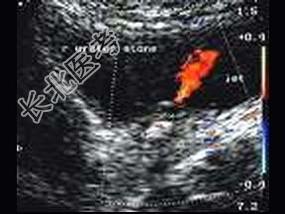

- 单项选择题图中所示为 ( )

A、膀胱血块

B、膀胱憩室

C、膀胱占位

D、输尿管喷尿征

E、以上都不是